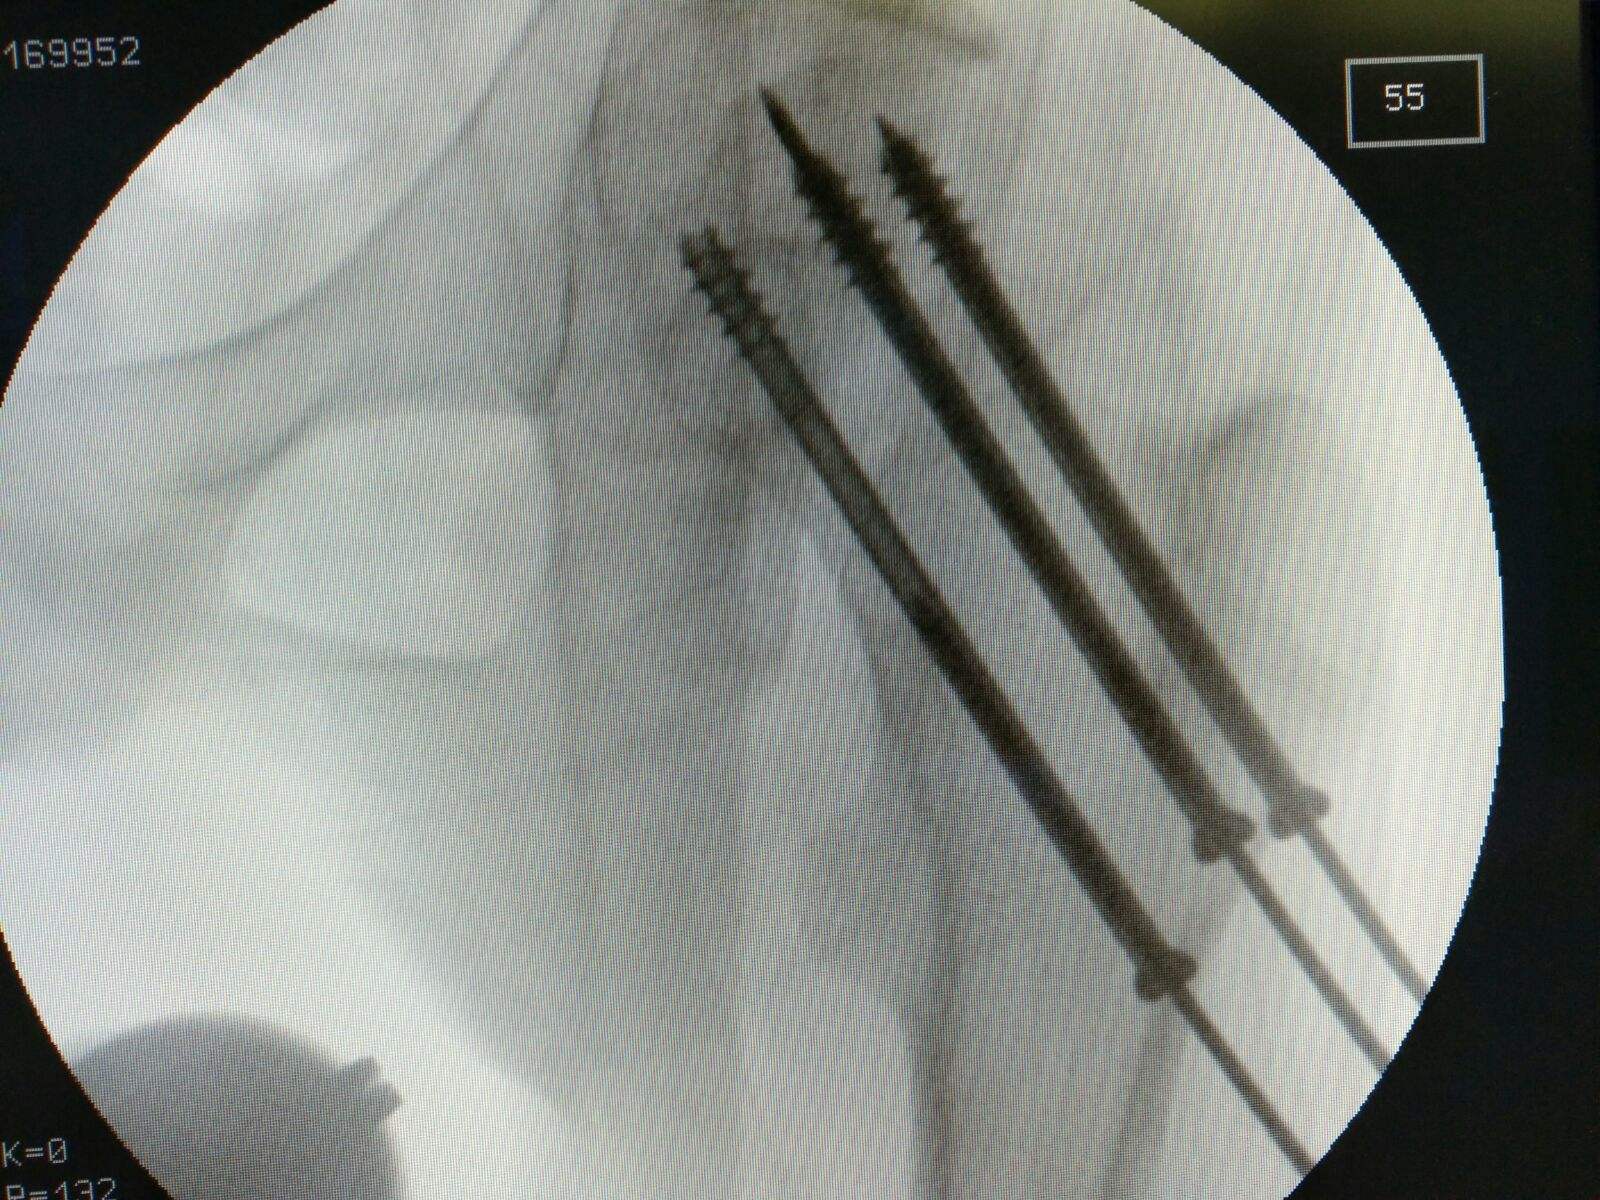

目前股骨颈骨折内固定最常采用 3 根空心钉固定,空心钉在股骨颈内 的空间构型要遵循平行分散和三点固定原则 。传统手术的进行需术者在术中透视下完成空心钉的置入,不仅操作难度高,且对术者手术技巧要求高,难以保证将空心螺钉置入理想方向与位置,

且股骨颈直径较小,徒手置钉常出现髓内钉穿出骨皮质或穿入关节腔内,因此常需多次钻孔及透视, 上述操作将会对患者产生二次伤害 ,增加了螺钉松动、骨折移位及骨折不 愈合等不良后果发生的几率。

而骨科机器人可通过 C 臂机获取患者信 息,并建立完整精确的三维信息,从而辅助术者在术前或术中设计手术方案,并由机器人完成空间位置配准 ,在术中将放置手术工具(如钻头、铣 刀等)精确放置于相应手术部位.

在定位精确不足时还可通过光学捕捉系 统进行精度补偿,从而为术者提供准确安全的螺钉通道 ,在骨科机器人已 钻削好的唯一通道中,术者可自主控制完成高精确度的内固定螺钉的置入。